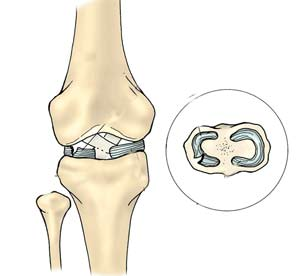

膝关节半月板损伤缝合修复术 医学百科

300x308 - 14KB - JPEG